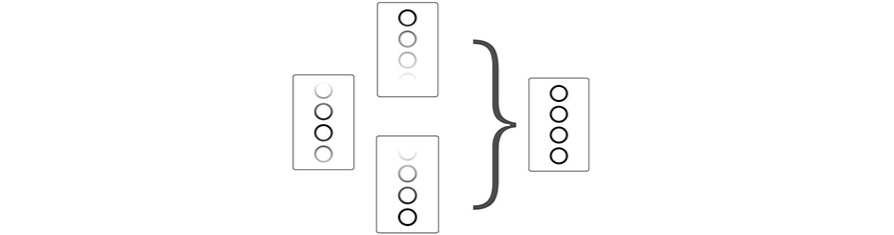

FCI (Frequency Compounding Imaging)

Permits compounding of different frequencies to form best whole field image homogeneity, providing better penetration especially for high frequency scan